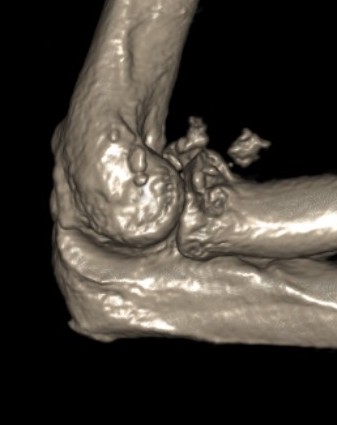

Elbow dislocation with concomitant fractures

Injury patterns

Terrible triad - elbow dislocation + MCL injury / coronoid process fracture / radial head fracture

Terrible Triad

Elbow dislocation with radial head fracture + coronoid fracture + MCL tear